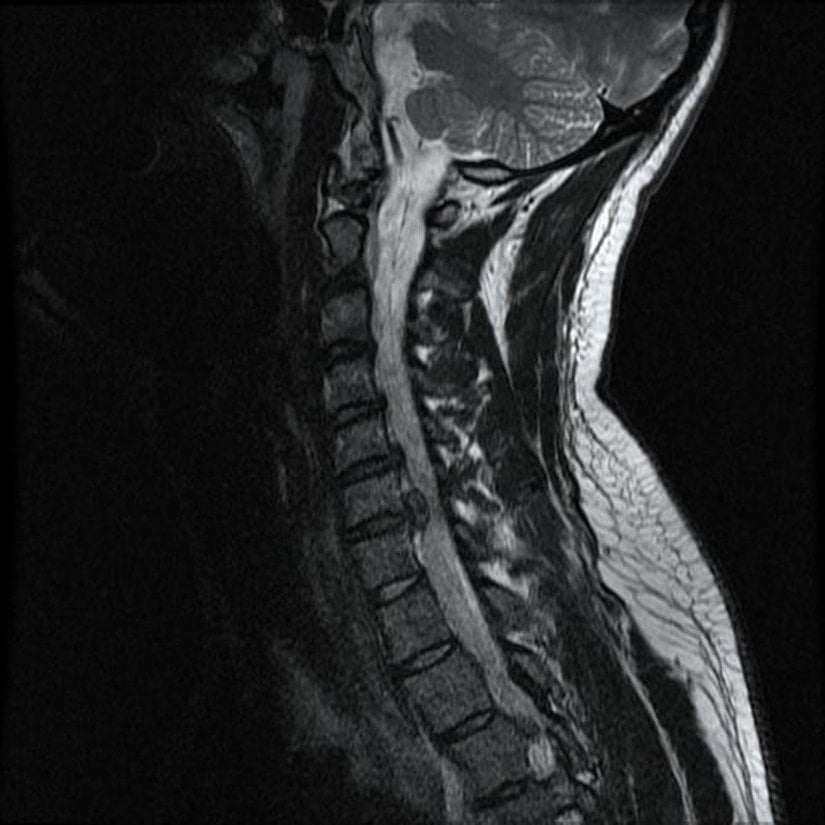

Acı nöroetiketi içerisindeki üye beyin hücrelerinin her biri, aynı zamanda diğer nöroetiketlerin bireyleri olabilirler. Eğer aklımızda "disk kayması" kavramına (ve bunun yarattığı acıya) karşılık gelen bir bilgi varsa, bu bilgi bir grup beyin hücresi ağı tarafından tutulmak zorundadır ve buna "disk kayması" nöroetiketi adını veririz. Dolayısıyla, bazı üyelerin hem disk kayması nöroetiketi içerisinde, hem de sırt ağrısı nöroetiketi içerisinde yer alması çok muhtemeldir. Bir diğer deyişle, eğer disk kayması nöroetiketini uyaracak olursak, sırt ağrısı nöroetiketinin de aktive olma şansını bir miktar arttırırız.

Bu modeli kullanarak, disk kaymasının sırt ağrısını potansiyel olarak tetikleyeceğini düşünebiliriz. Peki ya depoladığımız bilgi hatalıysa, tıpkı disk kaymasıyla ilgili bilgilerimizin hatalı olması gibi? Bir disk (veya omur), omurgaya öylesine sıkı bağlıdır ki, asla ve asla kayamaz. Buna rağmen, dilimizden ve buna yönelik yapılan görsellerden ötürü her birimiz "sırtımızdaki disklerin kayabileceğini" rahatlıkla ve güçlü bir biçimde iddia ederiz.

Bir insanın sırtıyla ilgili ağrılarını değerlendirmek için beyninin bu şekilde hatalı bilgileri kullandığı düşünülürse, bu insanın disk kayması ve bununla ilgili o korkunç klinik fotoğrafları görüyor ve düşünüyor olması, diğer tüm faktörleri eşit tuttuğumuzu sayarsak, bireyin sırt ağrılarını arttıracağını rahatlıkla ileri sürebiliriz.